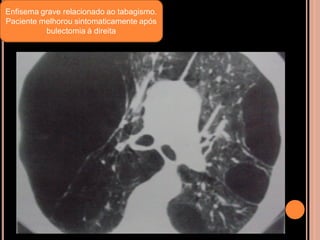

Enfisema grave relacionado ao tabagismo.

Paciente melhorou sintomaticamente após

bulectomia à direita